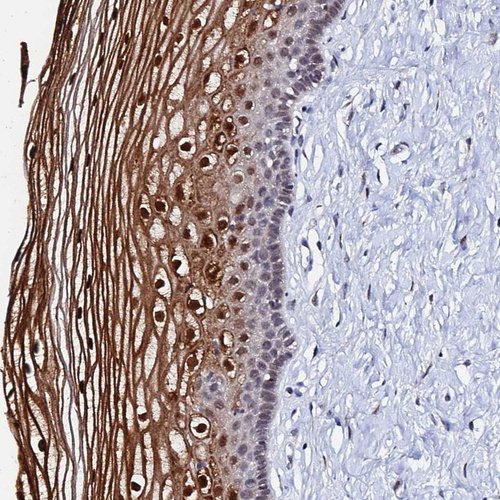

Immunohistochemical staining of human urinary bladder shows moderate cytoplasmic/nuclear positivity in urothelial cells with additional membranous positivity.